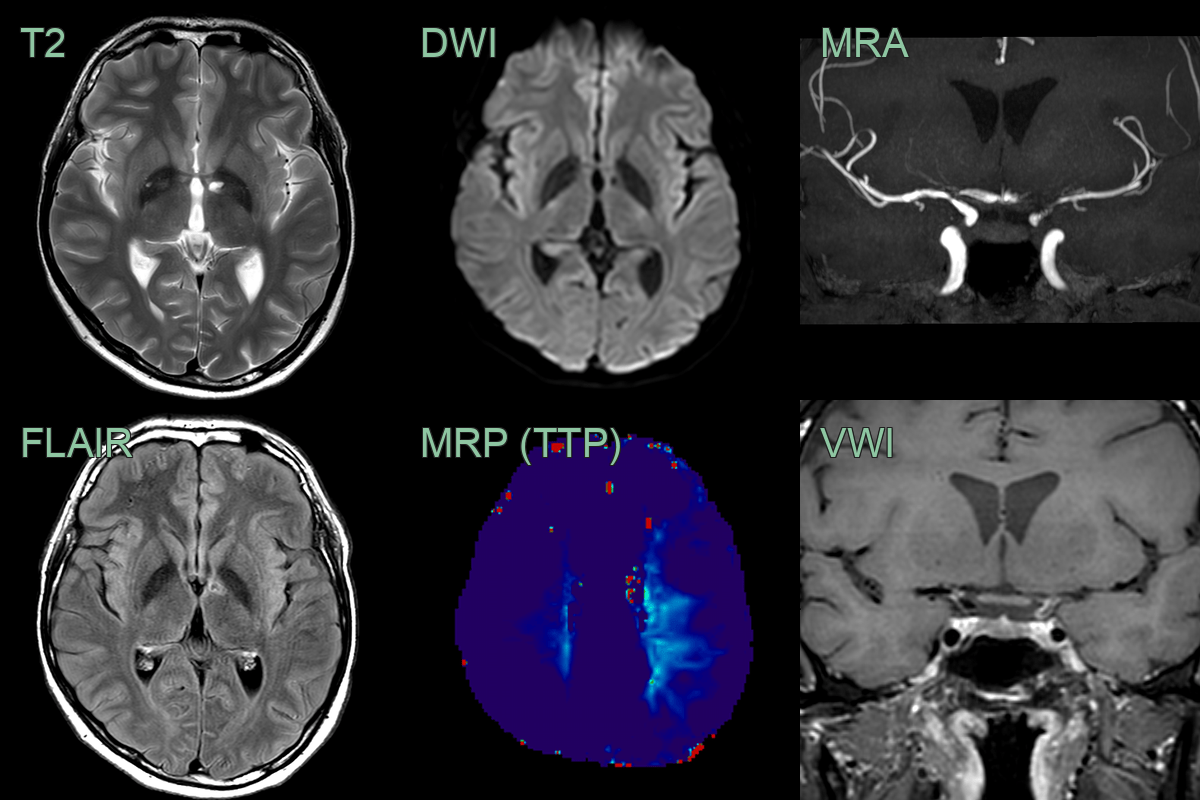

- A 35-year-old patient presenting with photophobia and headache was diagnosed with HIV with a CD40 count of 80.

- Baseline MRI showed an old infarct in the left thalamus. VWI imaging showed concentric enhancement within stenosis in the terminal ICA and MCA.

- Over the following 4-6 weeks, the mural enhancement was static. The stenoses only minimally progressed but the perfusion to the left and, to a lesser extent, right cerebral hemisphere worsened.